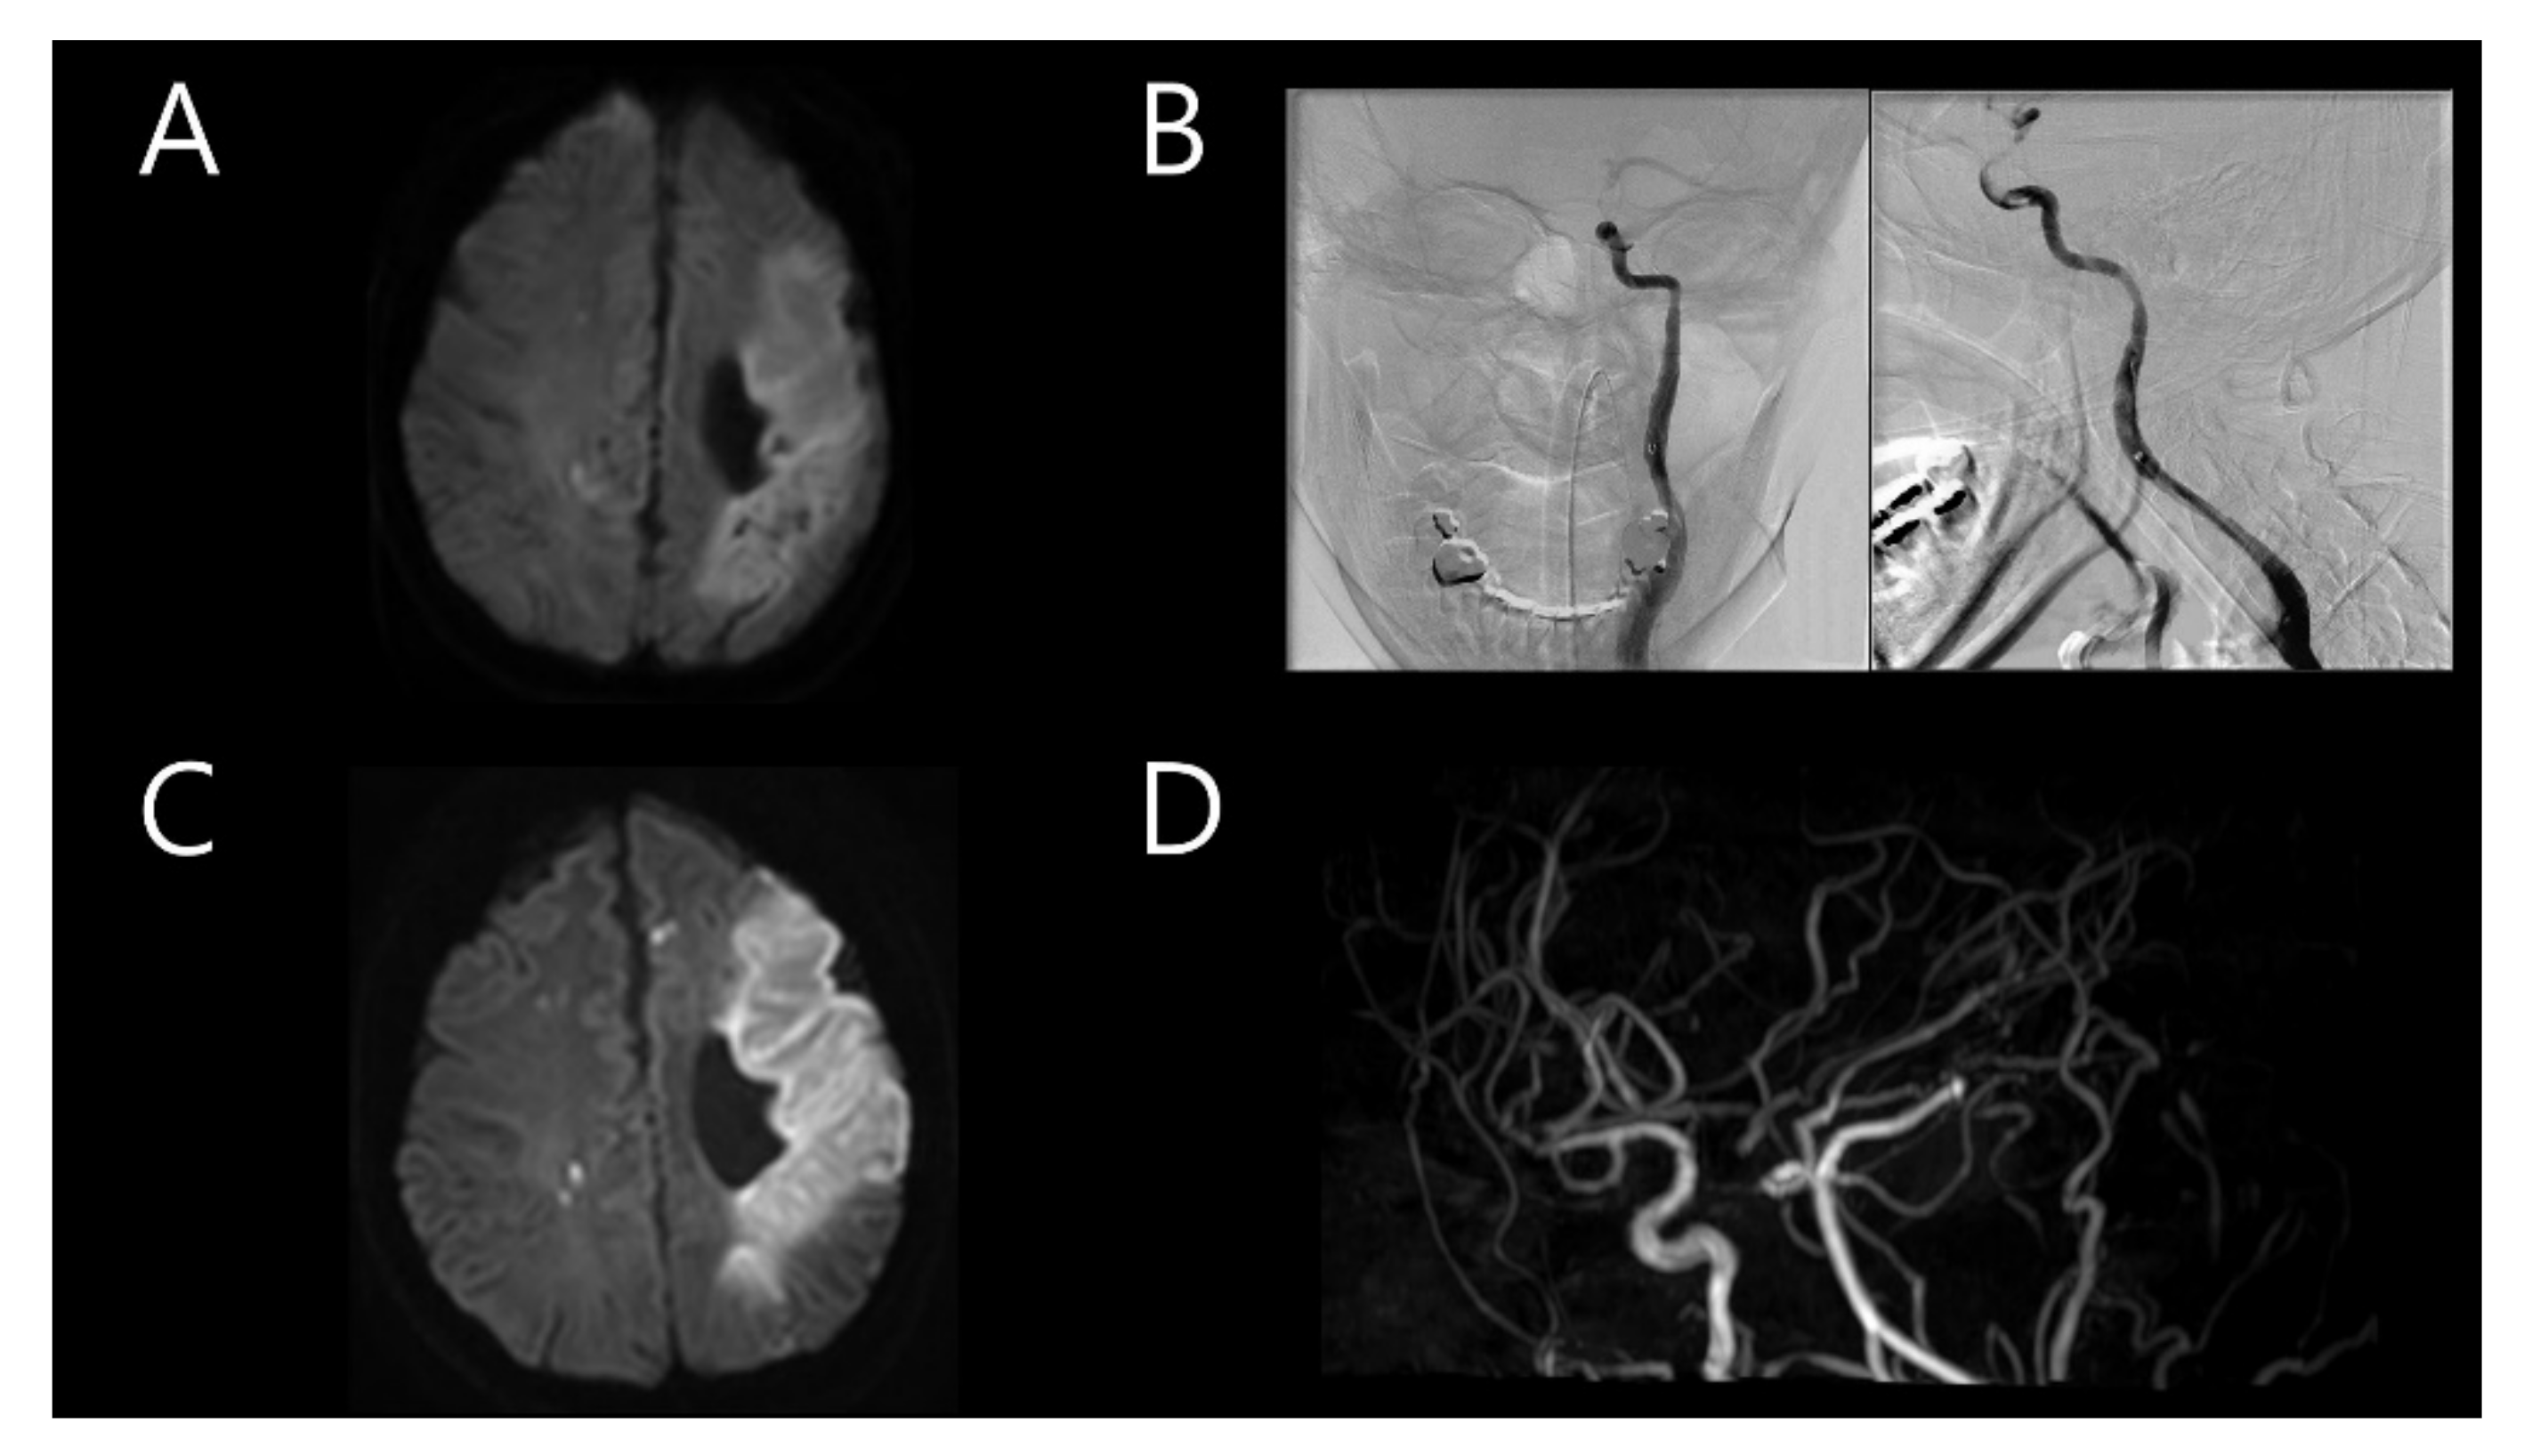

A 33-year-old woman was previously admitted with global aphasia at gestational week 7. She received daily injections of 2 cc of progesterone and low-molecular-weight heparin due to her history of two previous pregnancy losses at 25 and 28 weeks of gestation, respectively. These miscarriages each happened 2 and 3 years before the stroke, spontaneously after cervical ripening. Neurological examination revealed alert mental status, global aphasia, and right hemiparesis (Medical Research Council (MRC) grade, 3/3), indicating a National Institute of Health Stroke Scale (NIHSS) score of 11. Brain magnetic resonance imaging (MRI) revealed a stroke in the left middle cerebral artery (MCA) territory (Figure 1A). Intravenous tissue plasminogen activator (tPA) was administered, with an onset-to-door time of 1 h and 23 min. Intra-arterial thrombectomy was also subsequently performed. Transfemoral cerebral angiography (TFCA) revealed the total occlusion of the distal portion of the left internal carotid artery (ICA) with a massive thrombus. It was clearly a by-product of arterial dissection nearby; significantly, the operator felt the existence of the flap even before any further invasive procedure was practiced. However, the procedure could not be continued because of the severe headache experienced by the patient (Figure 1B). A brain MRI performed the following day revealed acute infarction in the left MCA territory with multifocal embolic infarction in the bilateral hemispheres and the complete occlusion of the left ICA (Figure 1C,D). Transthoracic echocardiography (TTE) used to verify the cardioembolic source revealed mild akinesia; however, the heart appeared normal on cardiac computed tomography (CT). The cardiac CT findings suggested acute pulmonary thromboembolism in the left lower lobe. Considering the massive thrombus in the left MCA and suspected pulmonary thromboembolism, warfarin was administered. Autoimmune disease screening tests, including those for anticardiolipin antibody and anti-beta-2 glycoprotein I antibody, were conducted twice, with negative results both times. Additionally, coagulopathy screening tests, including those for antithrombin antibody 87.7% (normal range 75–125), protein C antigen 111.8% (normal range 72–160), and protein S antigen 108.4% (normal range 60–150), were negative. The patient was discharged after her neurological symptoms improved (NIHSS score of 3).

Figure 1. (A) Initial brain magnetic resonance imaging (MRI) after the first event showing stroke in the left middle cerebral artery (MCA) territory. (B) Immediate transfemoral cerebral angiography showing total occlusion of the distal portion of the left internal carotid artery (ICA). (C) Follow-up brain MRI on the following day showing acute infarction in the left MCA territory with multifocal embolic infarction in the bilateral hemispheres. (D) Magnetic resonance angiography showing complete occlusion of the left ICA.